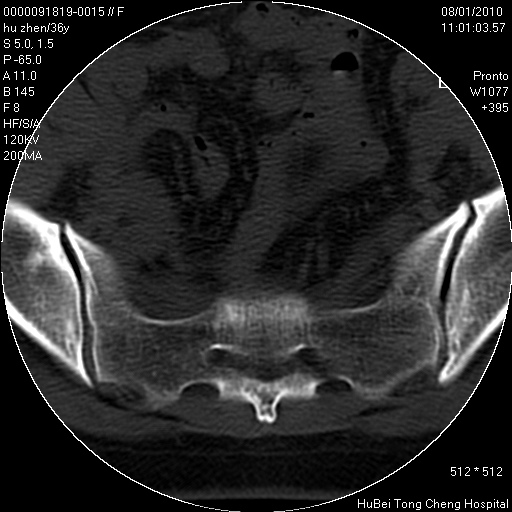

患者 女,36岁。右侧腰腿痛半月余。腰骶椎mr平扫偶然发现骶椎异常信号。

临床诊断:1)腰椎间盘突出症。2)骶椎肿瘤性病变?

骶椎ct平扫(层厚、层距均为5mm),图像如下:

考虑s1骨纤维异常增殖症。

良性改变,很难有明确答案。